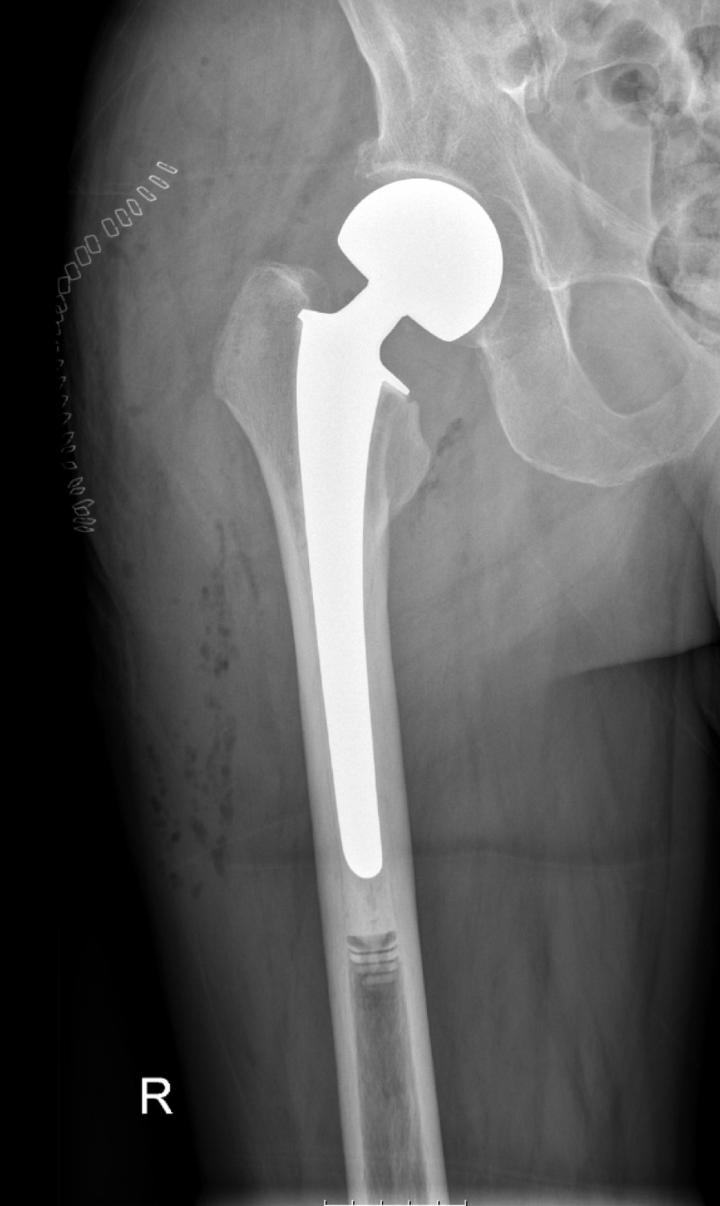

Fracture After Total Hip Replacement Orthopedic & Sports Medicine Can An Artificial Hip Pop Out  While hip dislocation is a major complication following hip replacement surgery, understanding the causes, risk factors, and preventive measures can significantly reduce the risk. Hip dislocation is a painful event in which the ball joint of your hip comes out of its socket. A loosening hip replacement implant can be painful. Dislocation after hip replacement is uncommon. Symptoms of a. Can An Artificial Hip Pop Out.